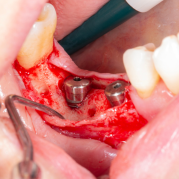

Diş çekiminin yıllar önce yapılmış olmasına bağlı olarak ince kemik varlığında implant ve kemik grefti uygulandı